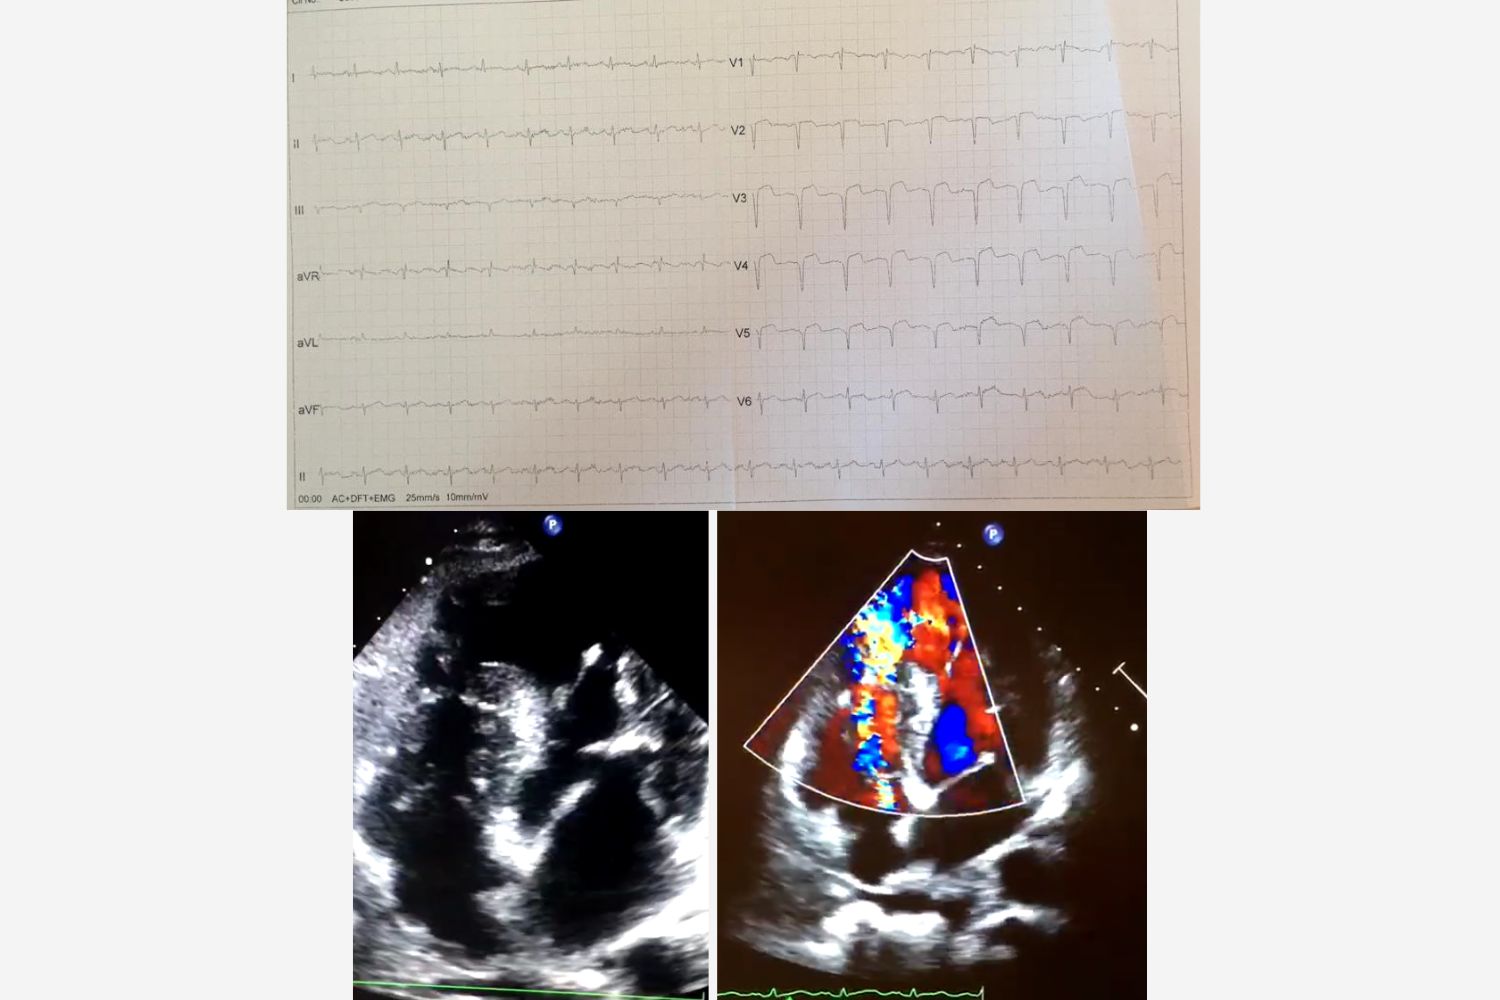

Image of the Week - 22 October 2025

Doctor Nur Rahma Almaraz

Doctor Elena Sufrate Sorzano

Miss Teresa Gonzalo Moreno